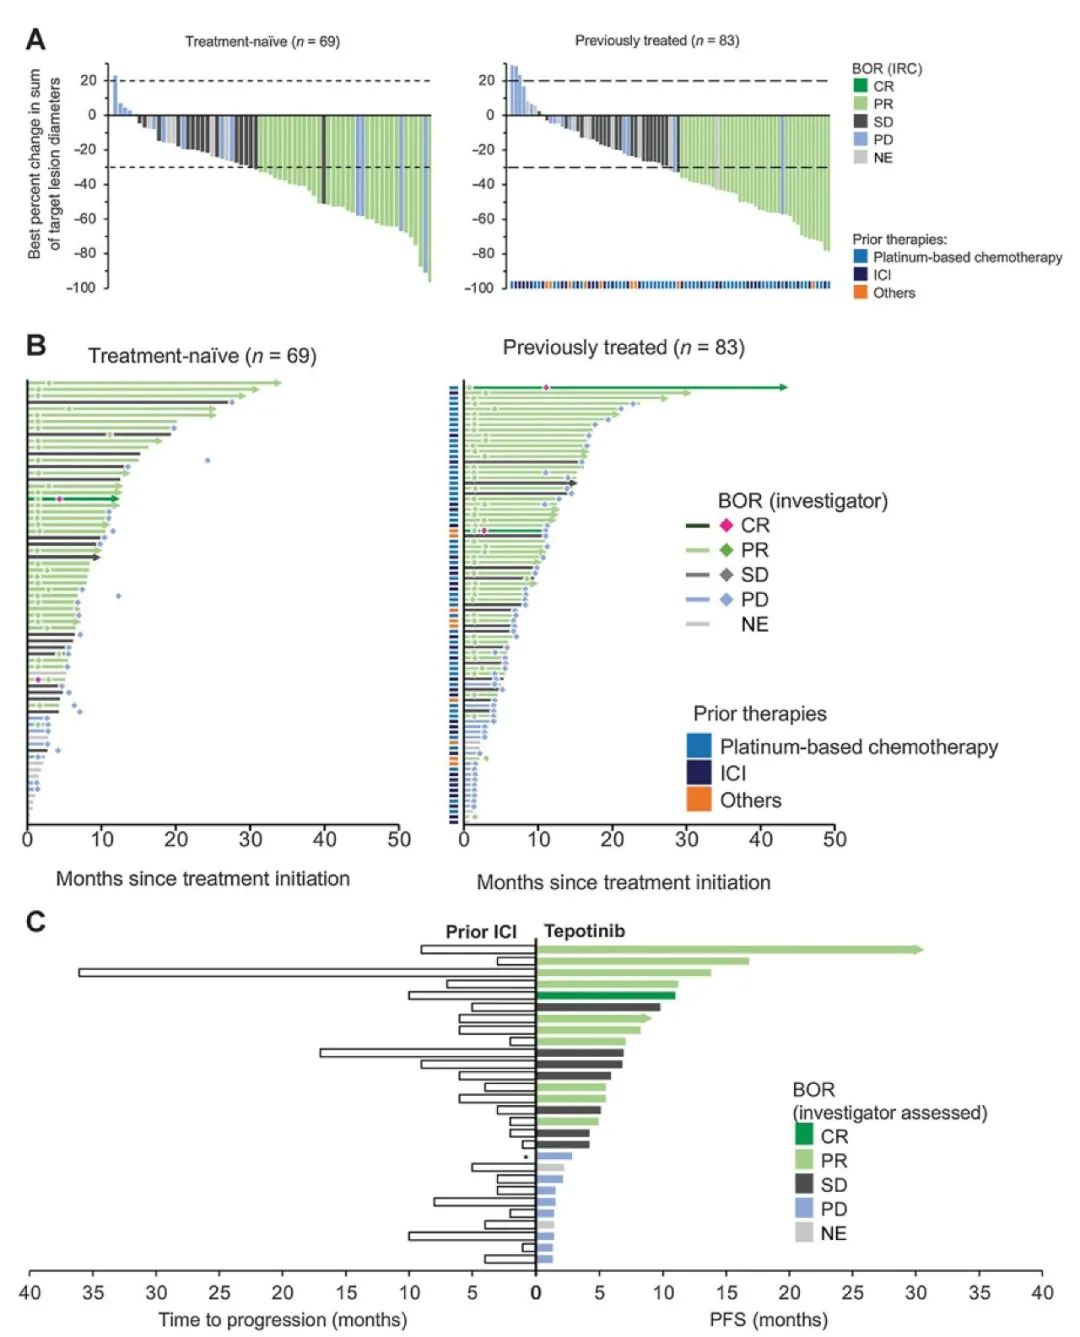

特泊替尼在MET 14外显子跳跃突变非小细胞肺癌中的疗效和安全性:VI...

特泊替尼在MET 14外显子跳跃突变非小细胞肺癌中的疗效和安全性:VI...